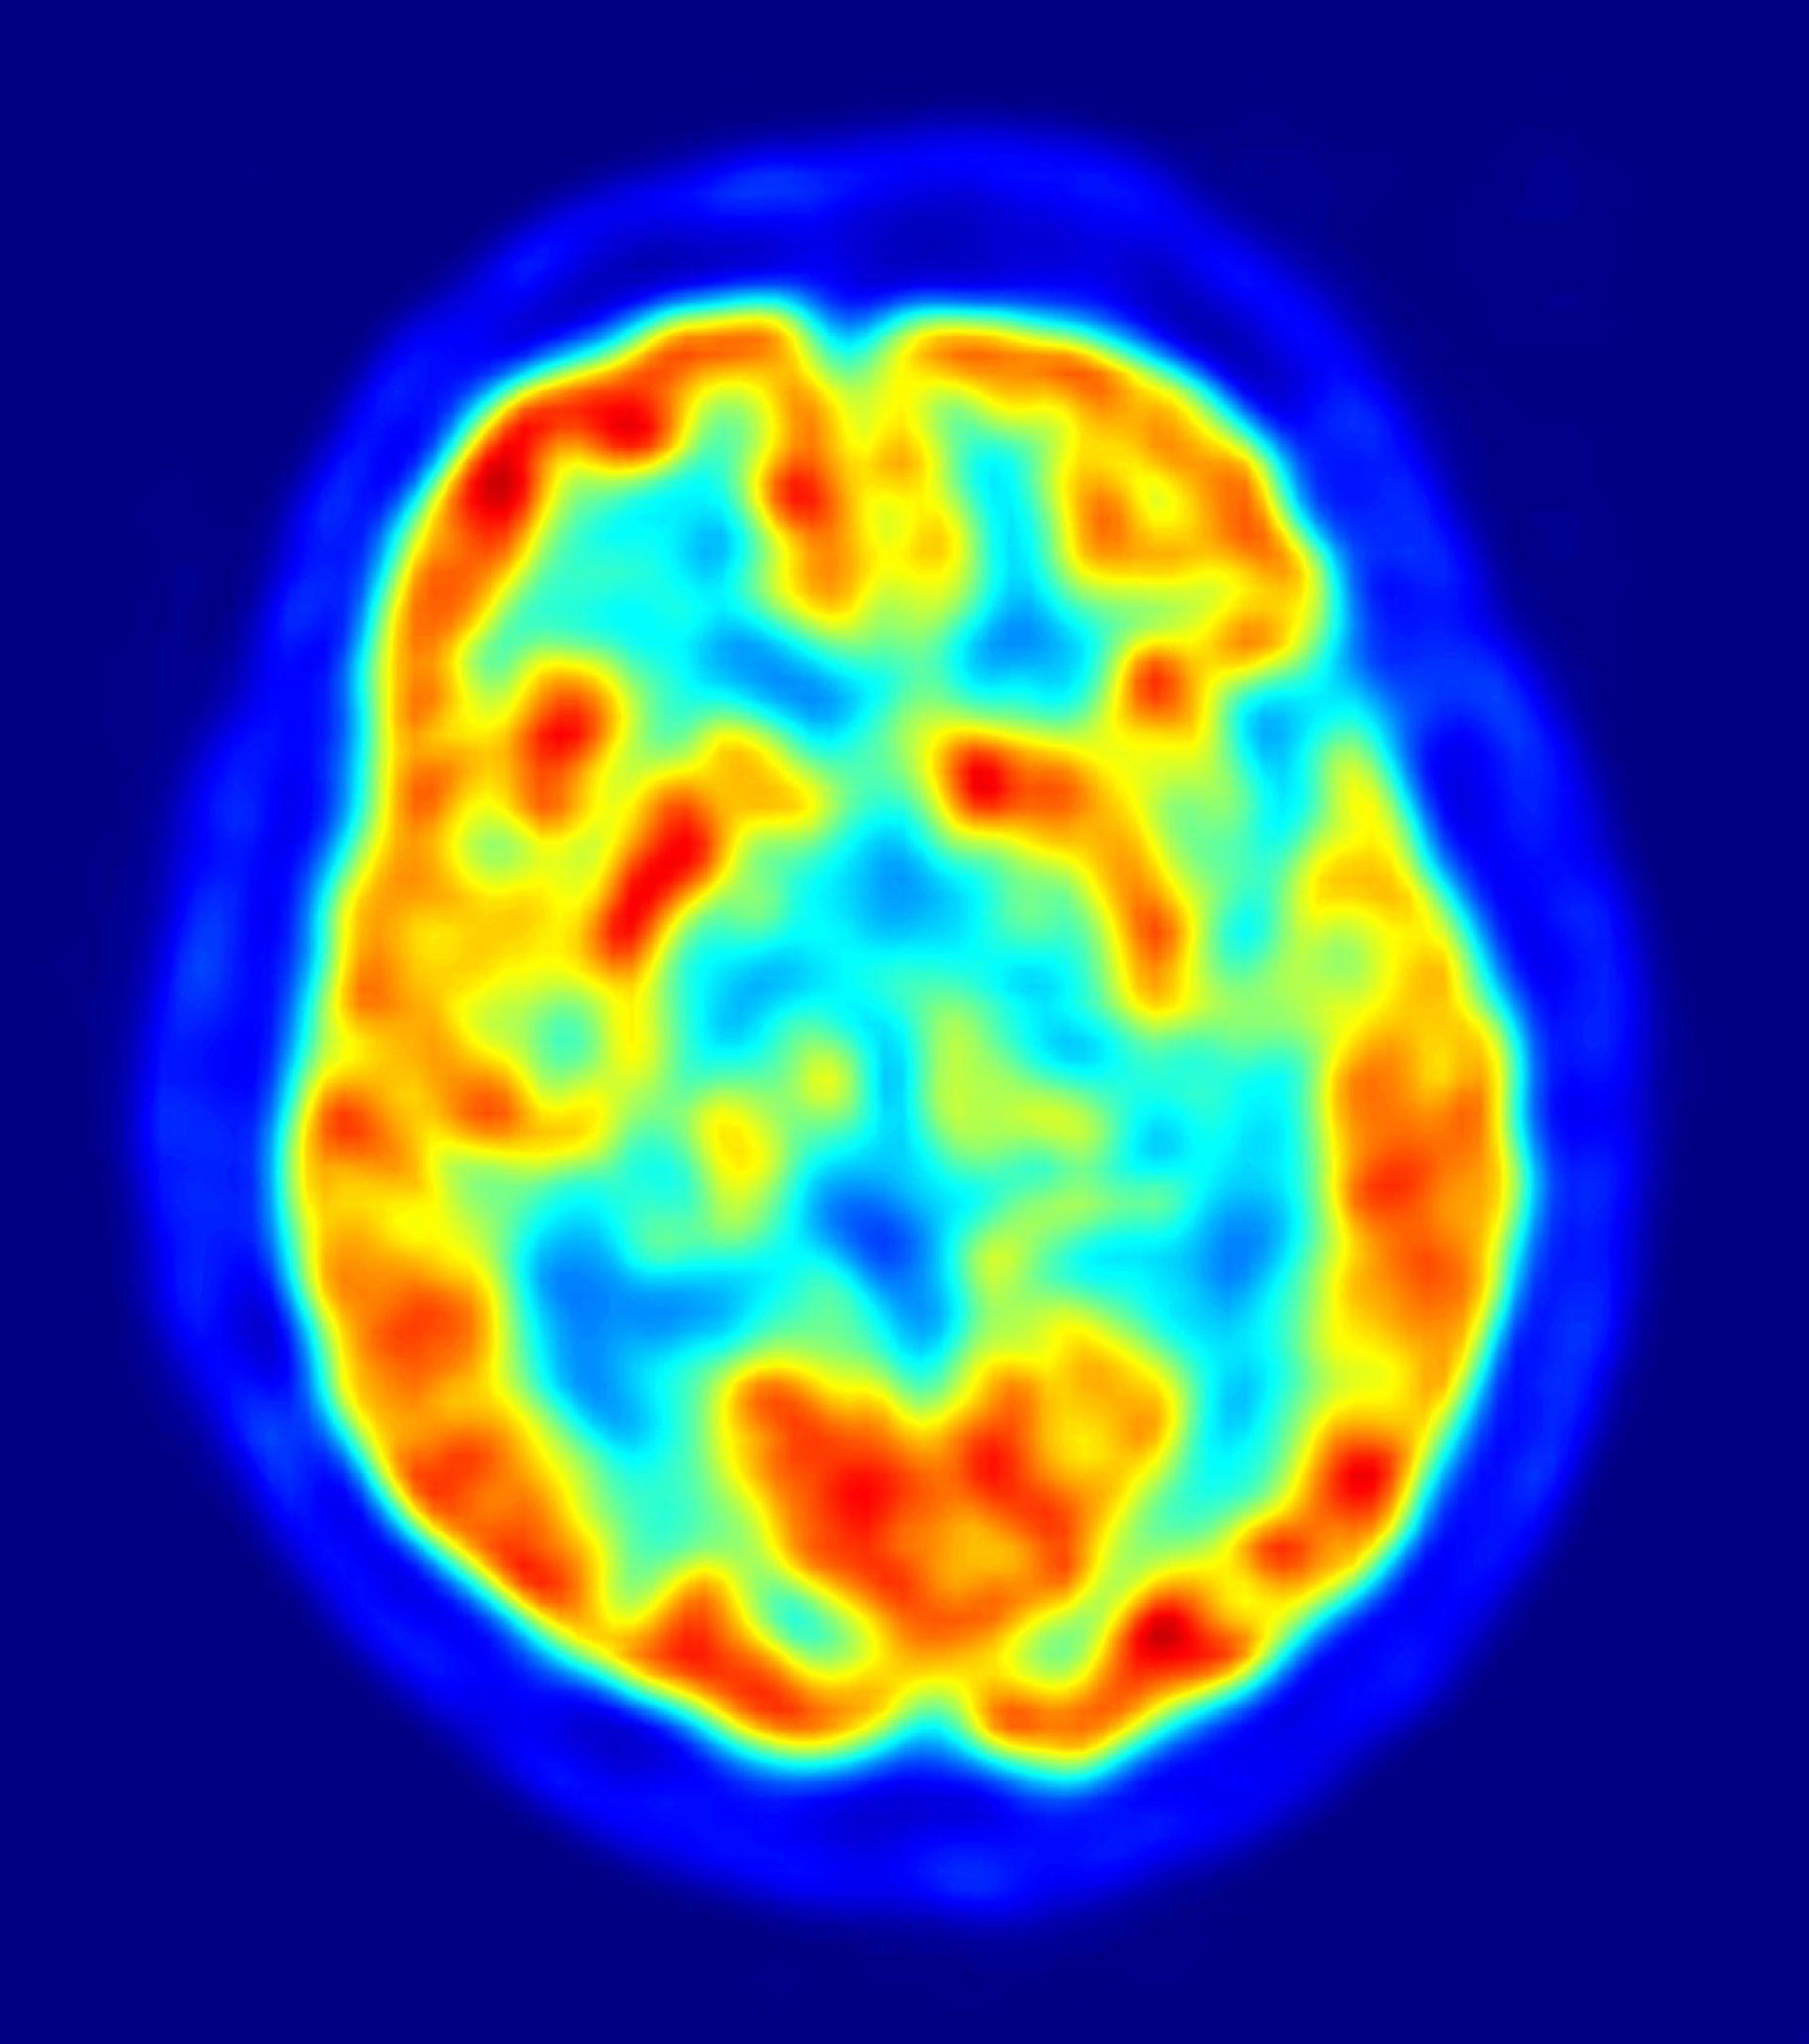

El neurocientífico y catedrático de la Universidad Autónoma de Barcelona (UAB) Ignacio Morgado ha explicado que la estimulación eléctrica será el tratamiento "más efectivo" para las enfermedades mentales. El Instituto de Neurociencia de la UAB lleva tiempo trabajando en la introducción de pequeñas corrientes eléctricas en el cerebro, similares a las que producen las propias neuras en funcionamiento.

Morgado ha explicado que el tratamiento de estimulación eléctrica, aplicado en su laboratorio a ratas y practicado en Canadá con personas depresivas y enfermos de Alzheimer por el científico de origen español Andrés Lozano, está dando resultados "asombrosos y muy esperanzadores".

"Al contrario que los tratamientos bioquímicos, la estimulación eléctrica no tiene efectos secundarios y la reacción es inmediata", ha explicado Morgado, quien también ha advertido de que este tratamiento no tiene nada que ver con el electroshock.